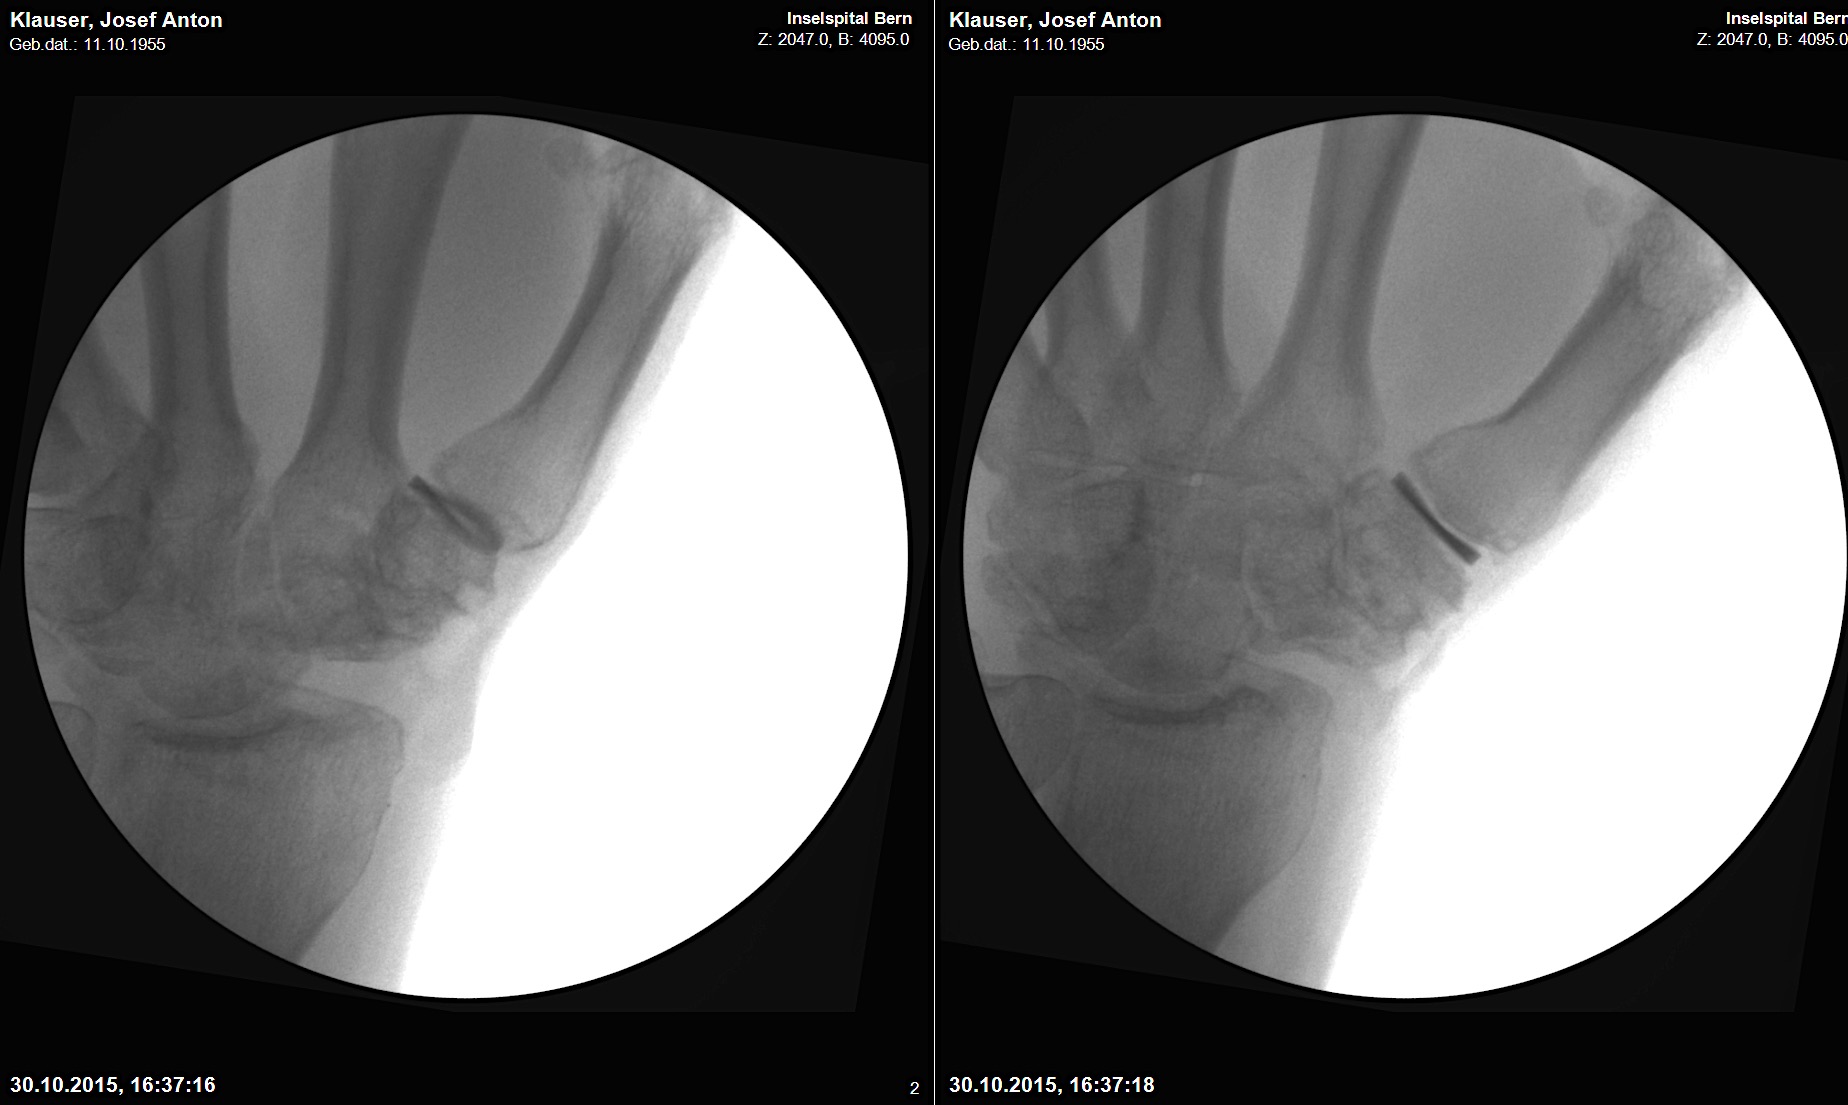

Case 3:

A 60-year-old male patient required an arthrodesis of the thumb carpometacarpal (CMC) joint after an implant arthroplasty in conjunction with the implantation of cortico-cancellous bone graft following a proximal row carpectomy and a previous arthrodesis between trapezium-trapezoid and the 2nd CMC joint (Fig 9). The first metacarpal dorsal plate from the VA Locking Hand System was selected for the procedure (Figs 10 - 11).